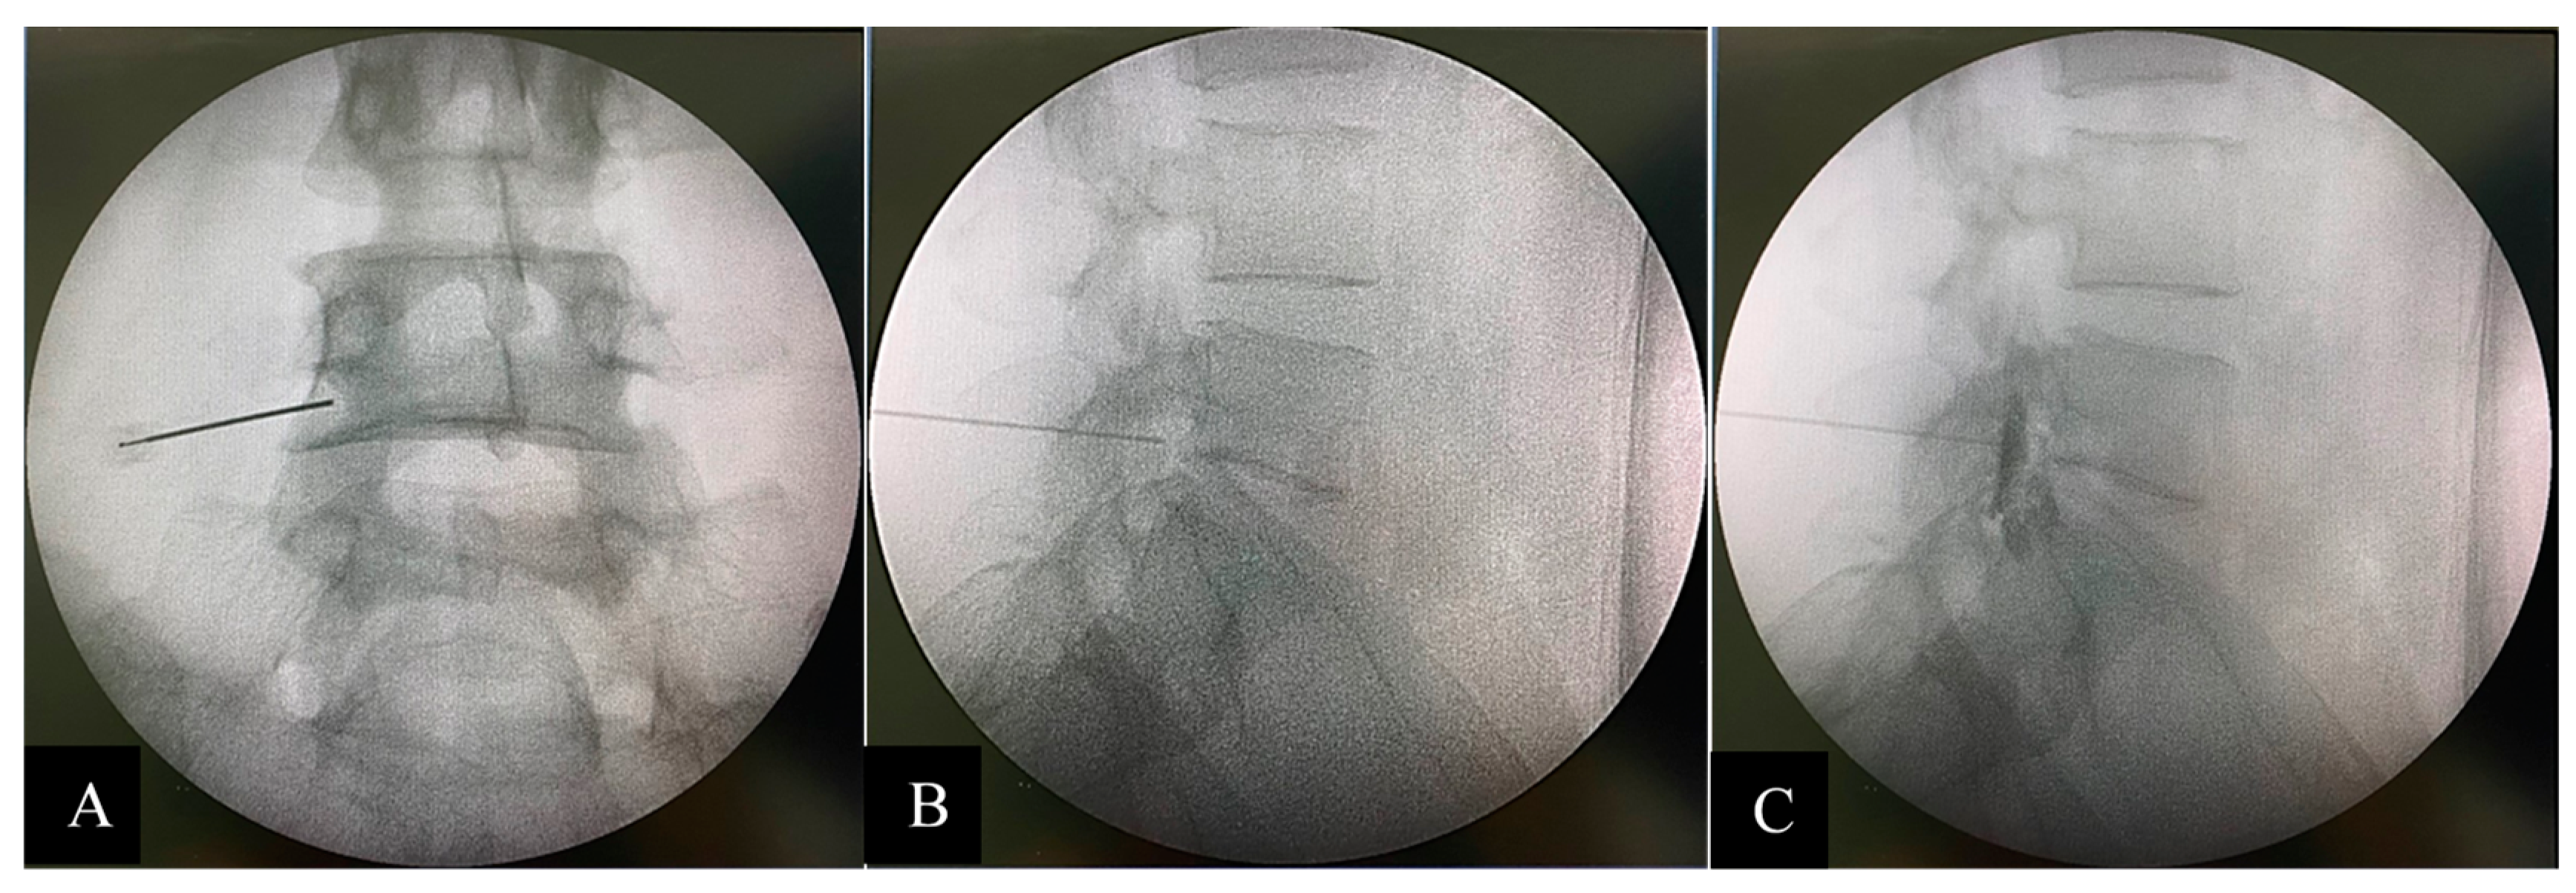

Two spine surgeons independently performed digital radiograph interpretations. The patients’ data and identifications were blinded to the evaluators. The sagittal parameters were measured by PACS (SYNAPSE, Fujifilm’s) measurement tools on the 27-inch monitor. Sagittal Vertical Axis (SVA), Thoracic Kyphosis (TK), Lumbar Lordosis (LL), Pelvic Incidence (PI), Pelvic Tilt (PT), Sacral Slope (SS), and PI-LL (PI minus LL) were measured according to the Scoliosis Research Society-Schwab classification[1]. C2C7 Cobb was measured from the angle between C2 and C7 lower endplate [20] (Figure 1).

Figure 1. Whole spine lateral standing films with measured sagittal parameters (A: pre-intervention, B: post-intervention).